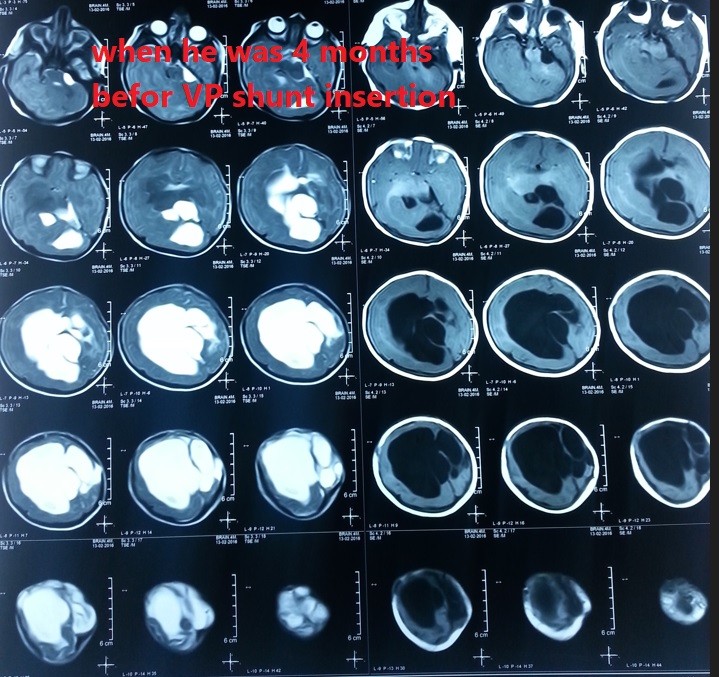

صور لحالة كاملة تم متابعتها منذ الأسبوع الأول من الولادة وحتي عمر ثلاث سنوات لطفل يعاني من قيلة مخية سحائية كبيرة .